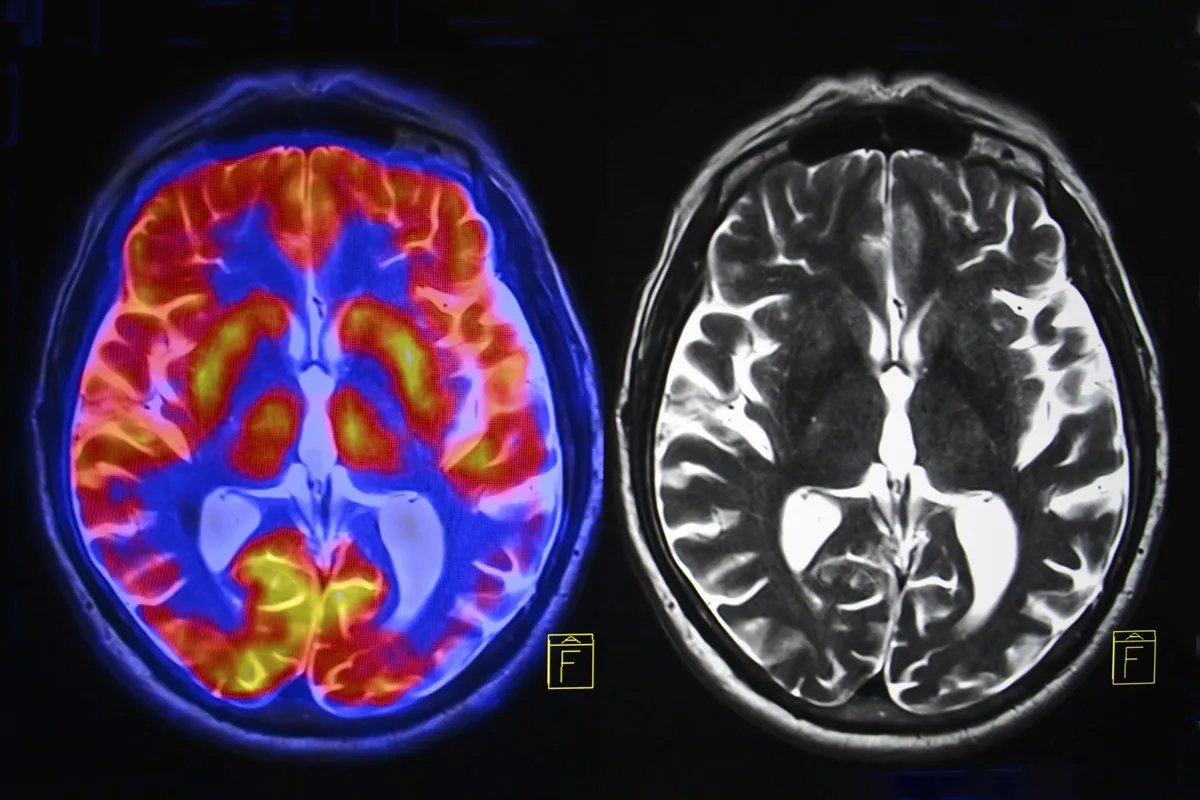

A landmark study of nearly 125,000 women has found that menopause is associated with measurable loss of grey matter in brain regions responsible for memory, emotion regulation, and decision-making. The findings, published in Psychological Medicine, offer the first large-scale evidence of structural brain changes during this life stage — and raise questions about long-term cognitive health.

The results were consistent across all post-menopausal women, regardless of whether they used HRT. The most significant shrinkage occurred in three regions: the hippocampus (which forms and stores memories), the entorhinal cortex (which acts as a gateway for information flow in the brain), and the anterior cingulate cortex (which helps regulate emotions and focus). These are the same regions vulnerable to Alzheimer's disease, which affects nearly twice as many women as men.